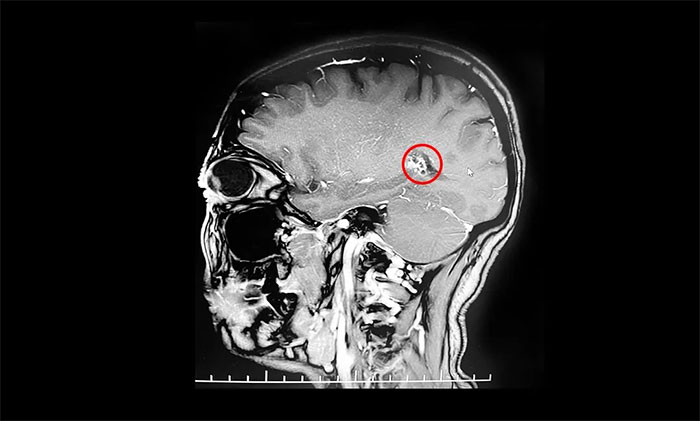

入院后,行海馬MRI平掃+MRS+MRSI檢查,MRS提示右側(cè)海馬Cho峰升高;掃及右側(cè)顳葉深部(側(cè)腦室顳角外下部)見一直徑約15mm類圓形異常信號(hào);右側(cè)側(cè)腦室顳角稍寬;颊呒韧哐獕翰∈4年,曾因右側(cè)顳部海綿狀血管瘤致蛛網(wǎng)膜下腔出血2次。楊忠旭教授結(jié)合患者癥狀,病史,磁共振、腦電圖等系列檢查,考慮海綿狀血管瘤及周圍皮層為致癲灶;颊咭呀(jīng)明確有反復(fù)出血史,手術(shù)指征明顯,需行手術(shù)切除治療,預(yù)防再次出血引起神經(jīng)功能及癲癇等癥狀。

▲ 海綿狀血管瘤